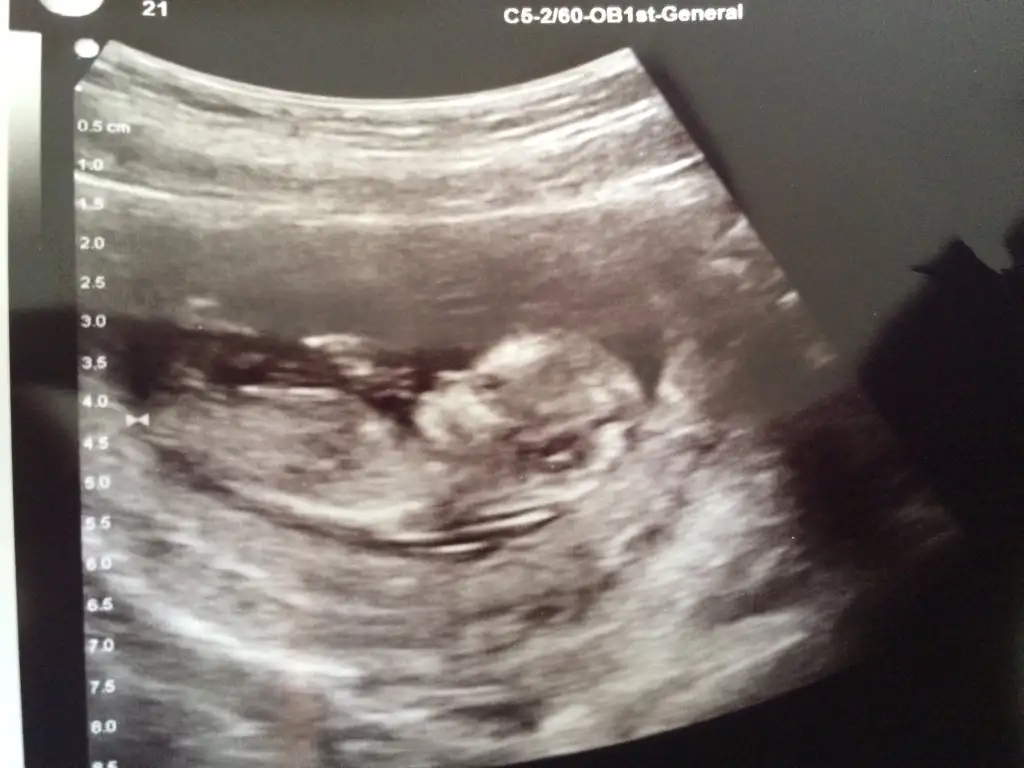

Bayanlar herkese selam ... Hastaneden geldim 11+5 biliyordum şimdi 12+2 olmuş :)) bebegim maşallah çok iyi ense kalınlığı felan iyi çıktı çok güzel pozlar verdi bebeşim yerim onu ben %65 erkek dedi canım oğlum diyeyim fotosunu paylaştım

Eklentiler

• image.webp

image.webp

29,4 KB · Görüntüleme: 135

maaşallah çok net görünüyor